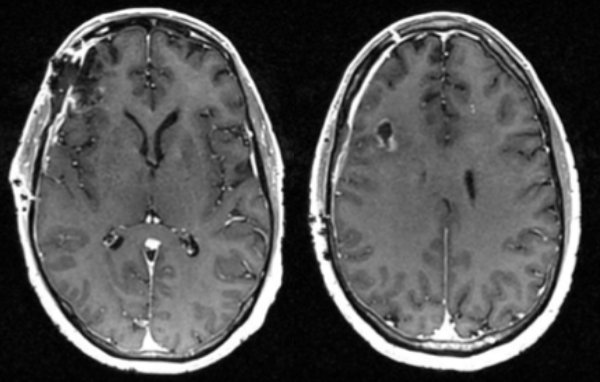

Post-op

Follow up imaging demonstrated a gross total resection for both intracranial metastases. The patient tolerated the surgery well and was discharged home on postoperative day four. At one-month follow-up, he was neurologically back to his baseline with a resolution of previous headaches and behavioral changes. He underwent postoperative stereotactic radiosurgery (Gamma Knife) to each surgical bed, followed by chemotherapy.